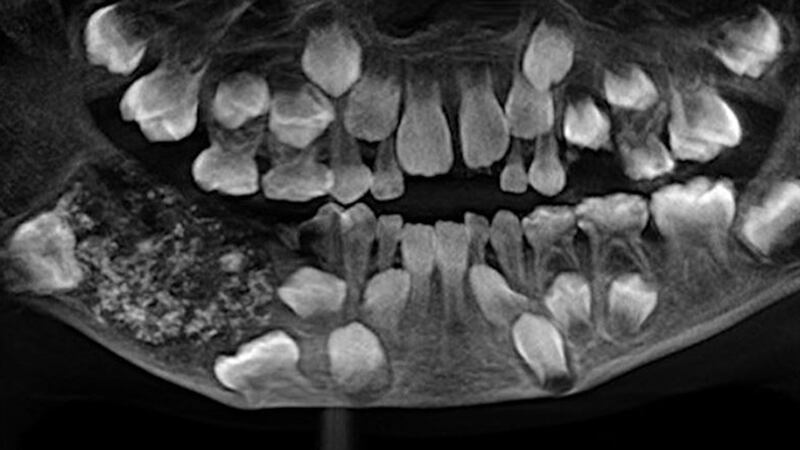

The boy underwent surgery last month at Saveetha Dental College and Hospital to remove the growth in his lower jaw, a news release from the hospital said. The baglike growth weighed about 200 grams and contained 526 teeth varying in size from 1 to 15 millimeters, according to doctors.

The 7-year-old boy was initially taken to a hospital in Chennai after complaining of jaw pain, hospital officials said. He was transferred to Saveetha Dental College and Hospital, where tests including CT scans revealed the tiny teeth in a tumorlike growth in his jaw, the Times of India and New Indian Express reported.